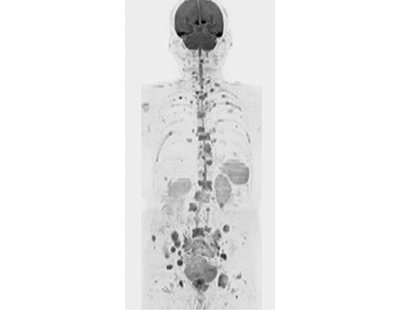

■症例2:前立腺がん肺転移・骨転移(body DWI)

89歳,男性。スライス厚:5.0mm,total scan time4:54,TR/TE:10812/78.8